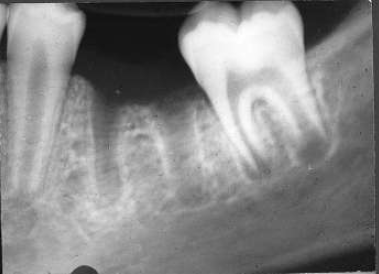

15. (Select ONE OR MORE correct answers)

Tooth 3.6 shows evidence of